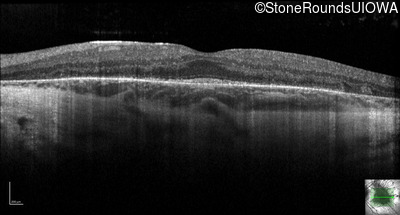

Optical Coherence Tomography - Right - 20/20 -3

Exemplar / OCT Stack

OCT Stack